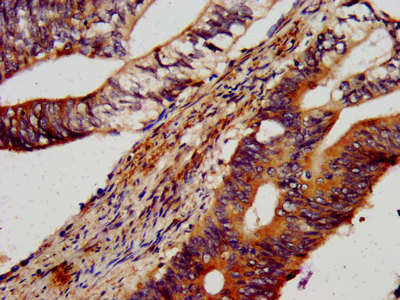

IHC image of CSB-PA652403LA01HU diluted at 1:600 and staining in paraffin-embedded human colon cancer performed on a Leica BondTM system. After dewaxing and hydration, antigen retrieval was mediated by high pressure in a citrate buffer (pH 6.0). Section was blocked with 10% normal goat serum 30min at RT. Then primary antibody (1% BSA) was incubated at 4°C overnight. The primary is detected by a biotinylated secondary antibody and visualized using an HRP conjugated SP system.